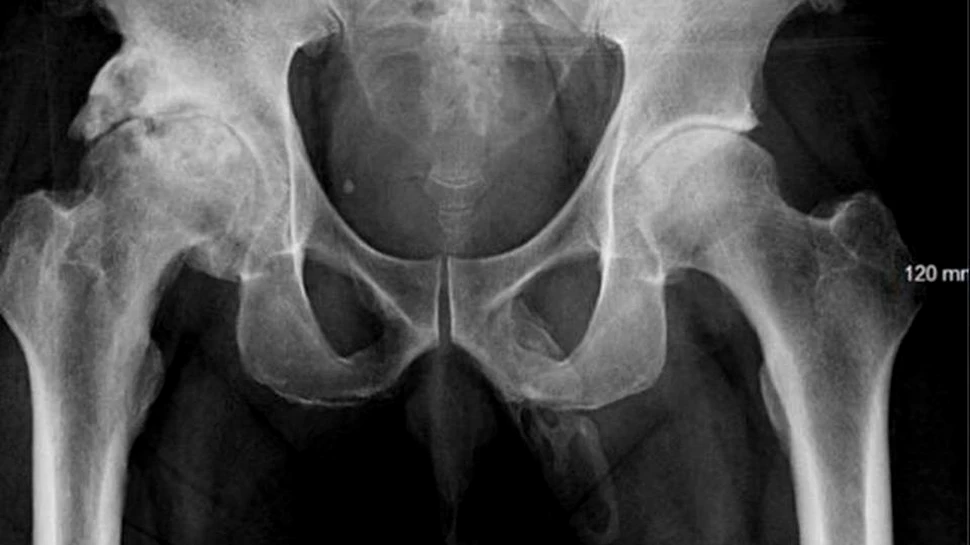

Din cauza faptului că bărbatul căzuse în posterior, medicii au decis să îl supună unui examinării cu raze X pentru a verifica dacă pelvisul acestuia a fost fracturat. După ce au primit rezultatele examinării, medicii au observat o masă osoasă care s-a format în interiorul penisului.

Credit foto: Georges El Hasbani şi ceilalţi autori ai studiului publicat în Urology Case Reports